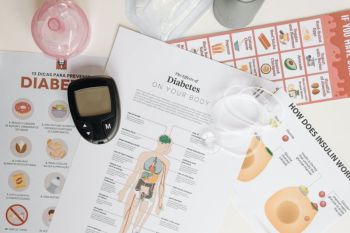

Dokter dari Rumah Sakit Mata Cicendo dr. Made Indra Widyanatha mengatakan, diabetes yang tidak terkontrol dapat ...